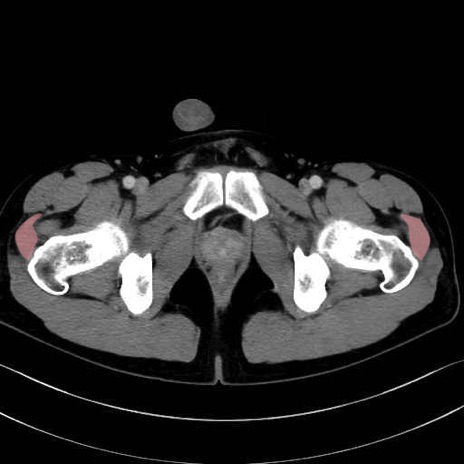

中殿筋 (Gluteus medius)